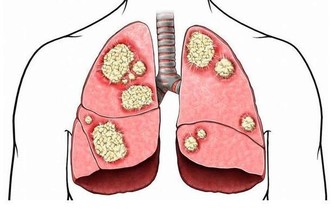

亂吃保健品吃出了病,甚至吃出癌症都是有可能的。

英國科學癌症研究中心研究了世界各地1000餘名30歲-50歲的癌症患者,

發現99.3%的人常年熬夜,凌晨後才會休息。

熬夜一方面會造成生物鐘紊亂,另一方面,夜間燈光會破壞人體褪黑素形成,

而這是保護人體免疫功能的重要一環,缺少它容易讓白血病、乳腺癌、前列腺癌等找上門來。